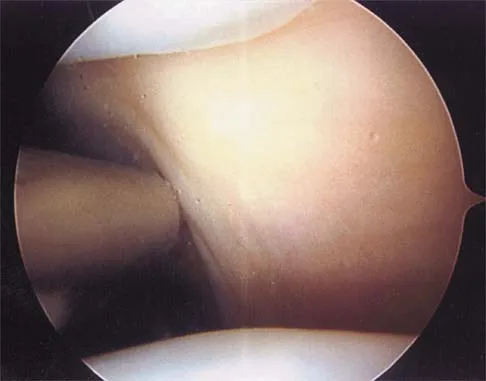

With a full-thickness articular cartilage injury, the body's healing response produces cartilage mainly composed of what type of collagen?